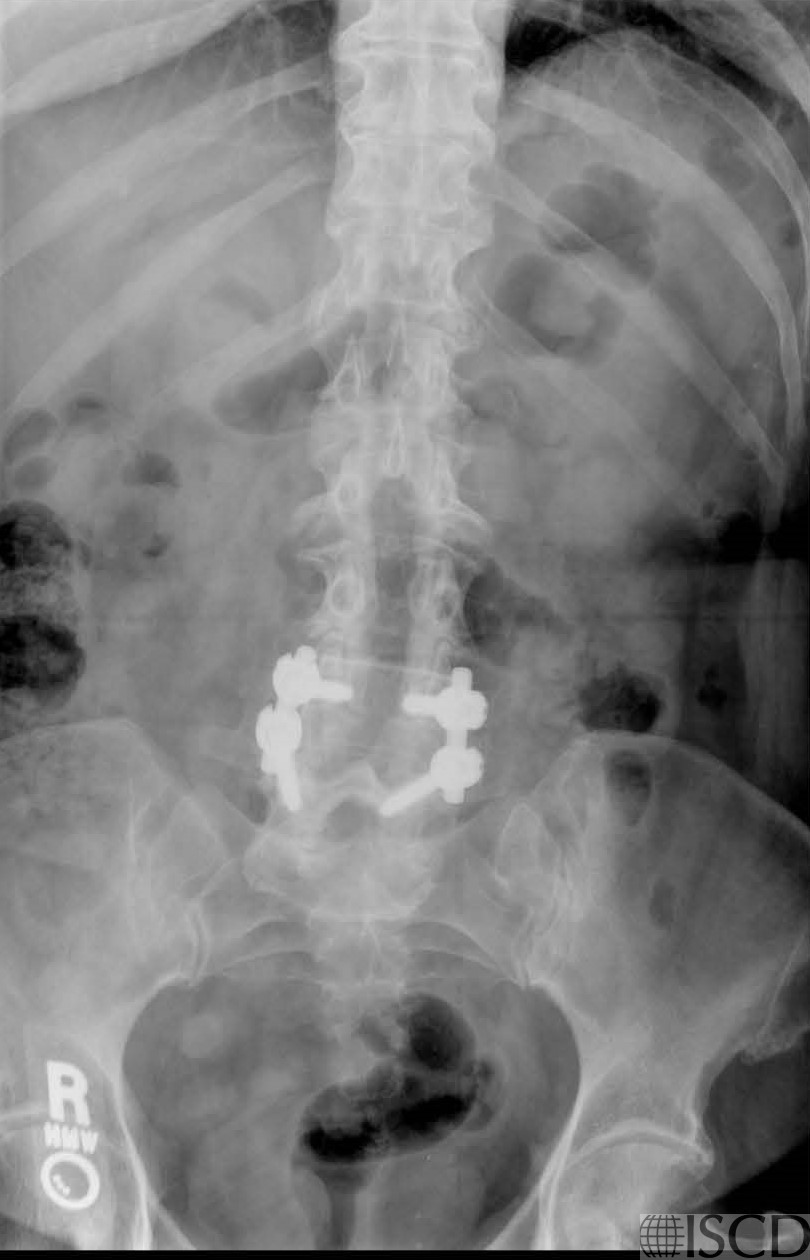

The lumbar spine DXA shows a laminectomy and spinal hardware. Because there is only one useable vertebral body the spine will not be reported and a wrist scan should be added.

The accompanying radiograph shows the laminectomy and spinal hardware.

Laminectomy and spinal hardware are seen on the DXA image and the accompanying radiograph. Because of the presence of laminectomy and hardware, the spine will not be useful in diagnosis and follow-up.